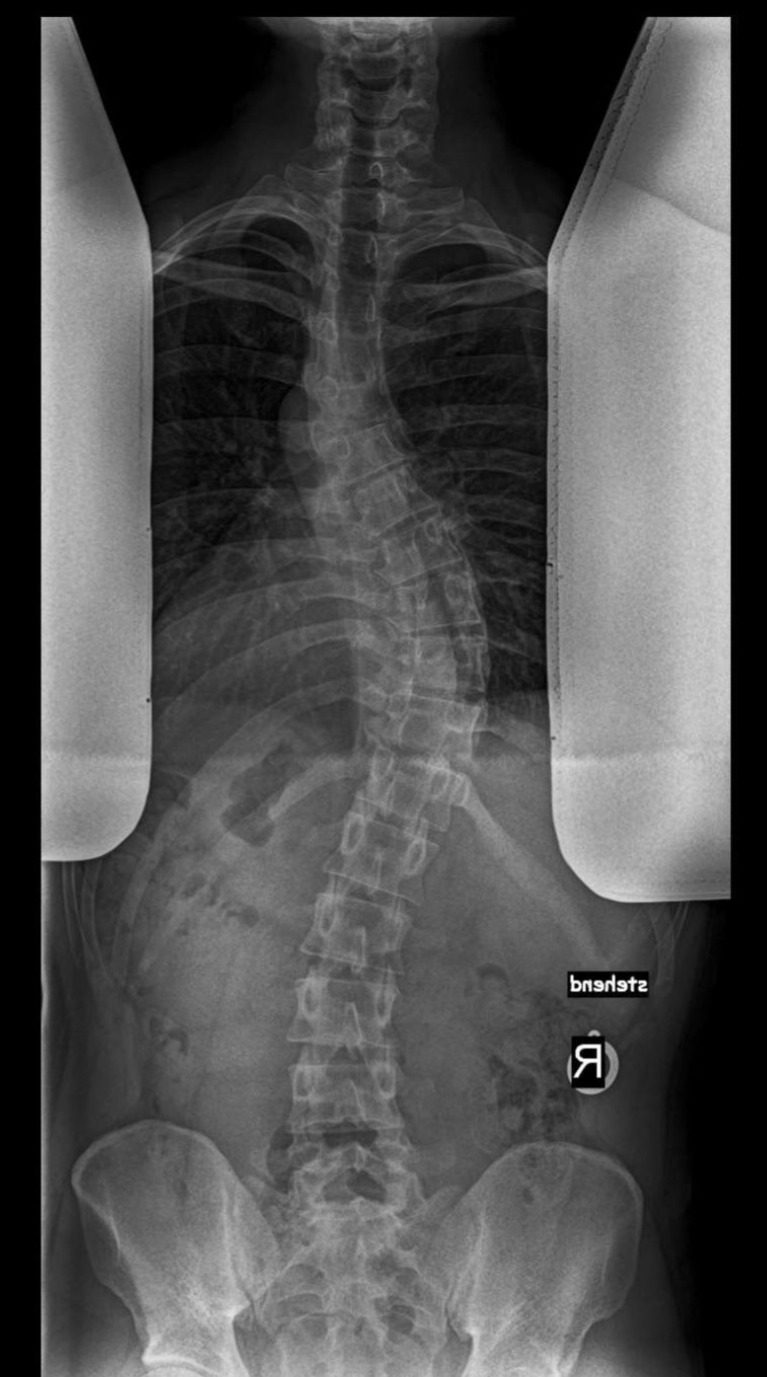

Skoliose ist eine dreidimensionale Verdrehung der Wirbelsäule, die sowohl bei Jugendlichen als auch bei Erwachsenen auftritt. In meiner Praxis zwischen den Orten Markt Erlbach und Neuhof an der Zenn liegt der Fokus auf einer spezialisierten, ganzheitlichen Behandlung nach Schroth – ergänzt durch Spiraldynamik und funktionellem Training.

Jede Skoliose ist unterschiedlich – sowohl in Ausprägung (Cobb-Winkel) als auch in der Lage der Krümmung.